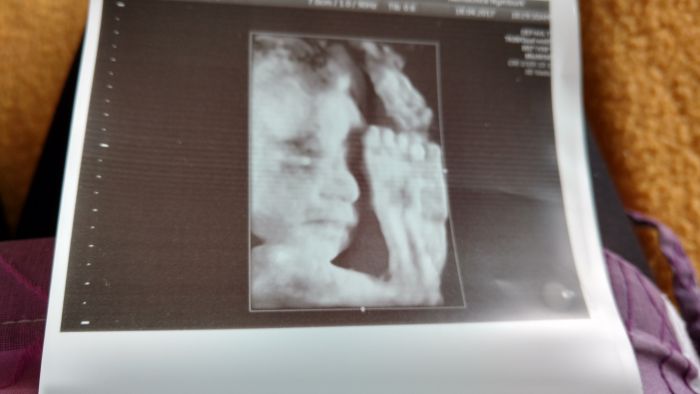

Ahoj děvčata, hlásím se po mém prvním 3D ult u tohoto cvrčka, teda poprvé protestoval, obě ruce před obličejem, dr.mě nechal se ještě překulit a pak ještě projít a pomohlo to, máme alespoň malou vzpomínku, ale je na chlup stejný jako dcerka na 3D ult, jsme si dělali legraci, že jsem tam vlastně vůbec nemusela chodit